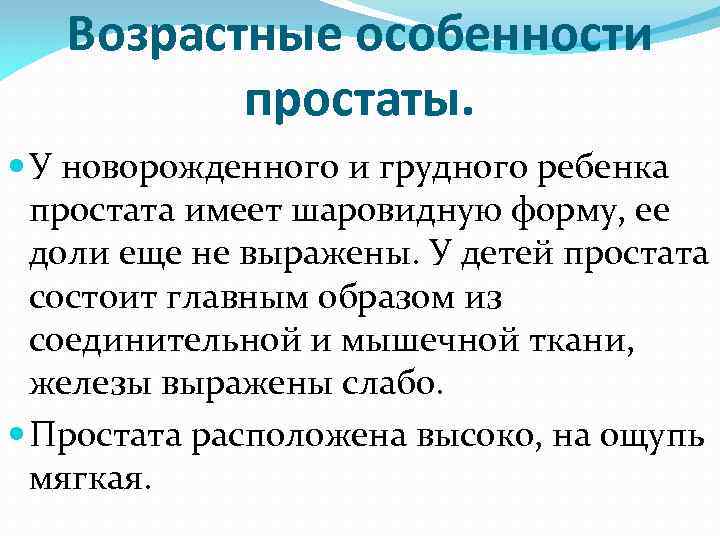

Простата детей